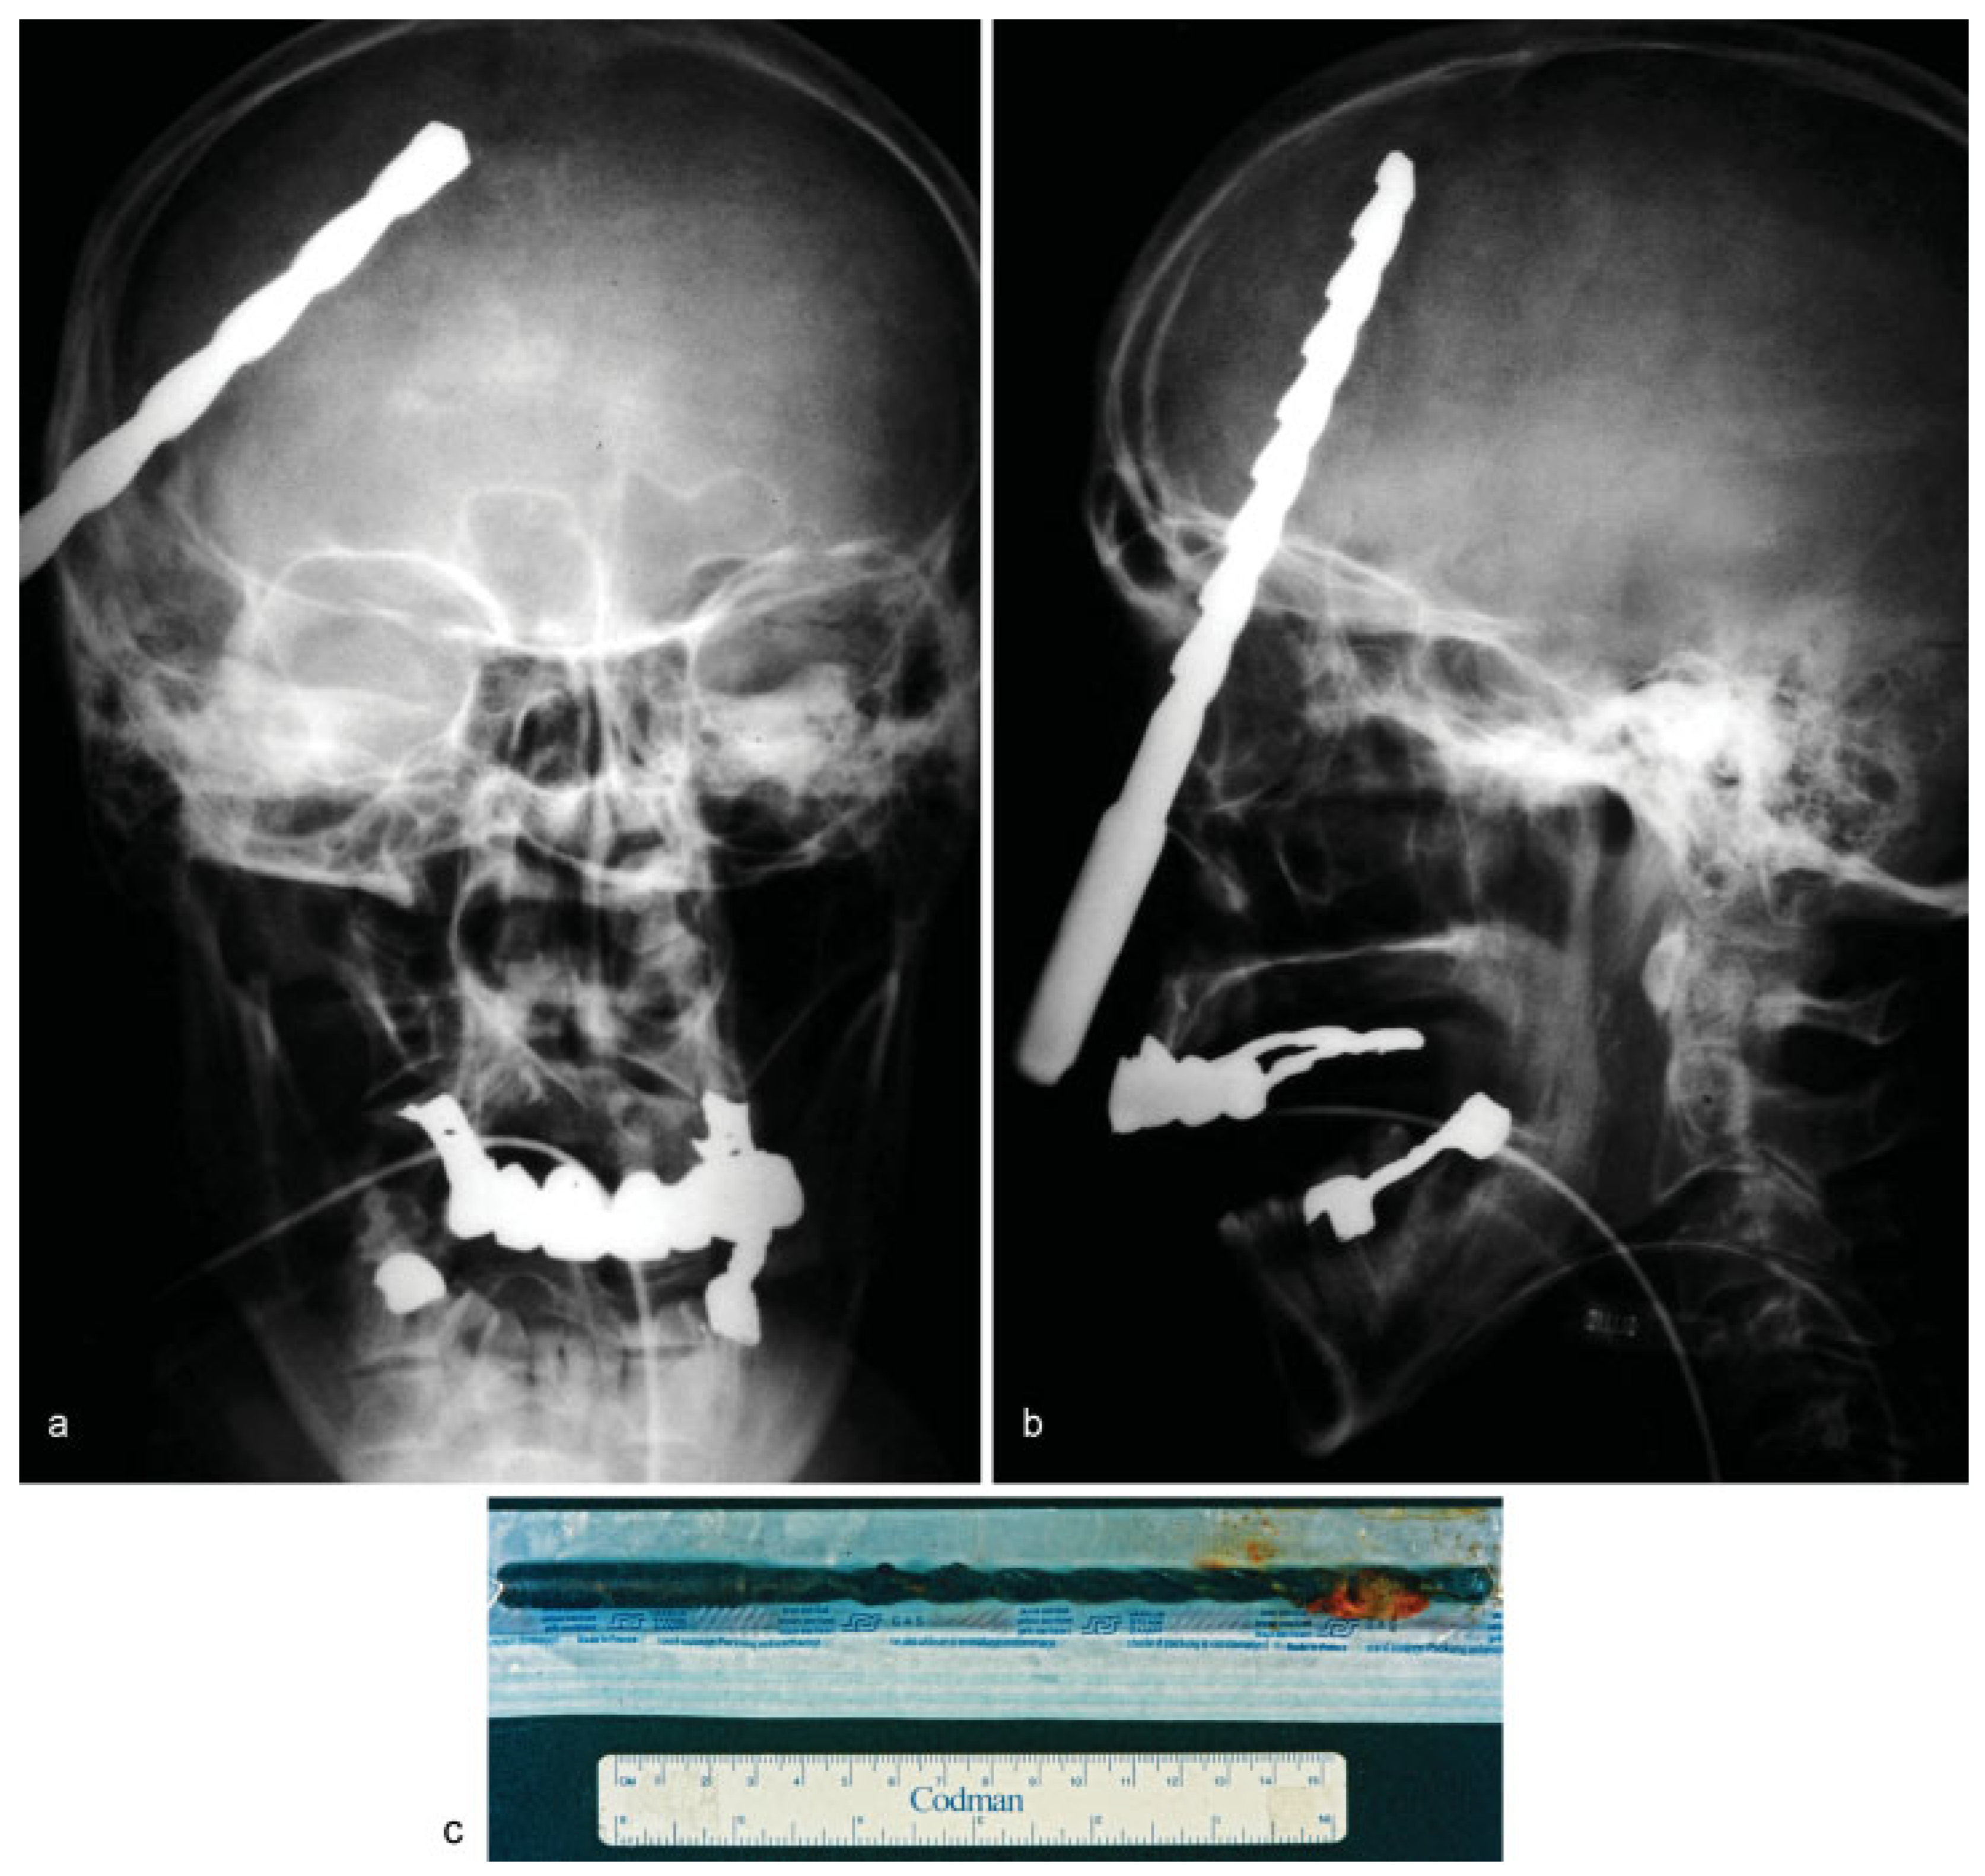

• Case 3: A 64-year-old patient shot himself by accident while handling a self-made rat trap in Turkey. Four days later, the patient travelled back to Germany on his own and visited the emergency department. Aside from multiple skin lesions, mainly around the periorbital region, clinical examination including ophthalmological assessment was uneventful, with the patient reporting only slightly blurred vision. Conventional X-ray demonstrated the presence of multiple shotgun projectiles throughout the soft tissue of his face (Figure 3a,b). In total, 46 projectiles were removed transcutaneously guided by intraoperative navigation and a C-arm X-ray, and assisted by ophthalmologists (Figure 3c). One projectile, located close to the superior orbital fissure, was left in place to prevent further damage (not shown). Postoperatively, the patient’s sight was undisturbed and healing proceeded normally. To our knowledge, no complications related to the remaining projectile have been noted.

Figure 3. (a,b) Frontal and lateral skull radiographs showing multiple radiopaque round foreign bodies spread over the face entering the orbital funnel. (c) Postoperative picture of a single shotgun pellet.